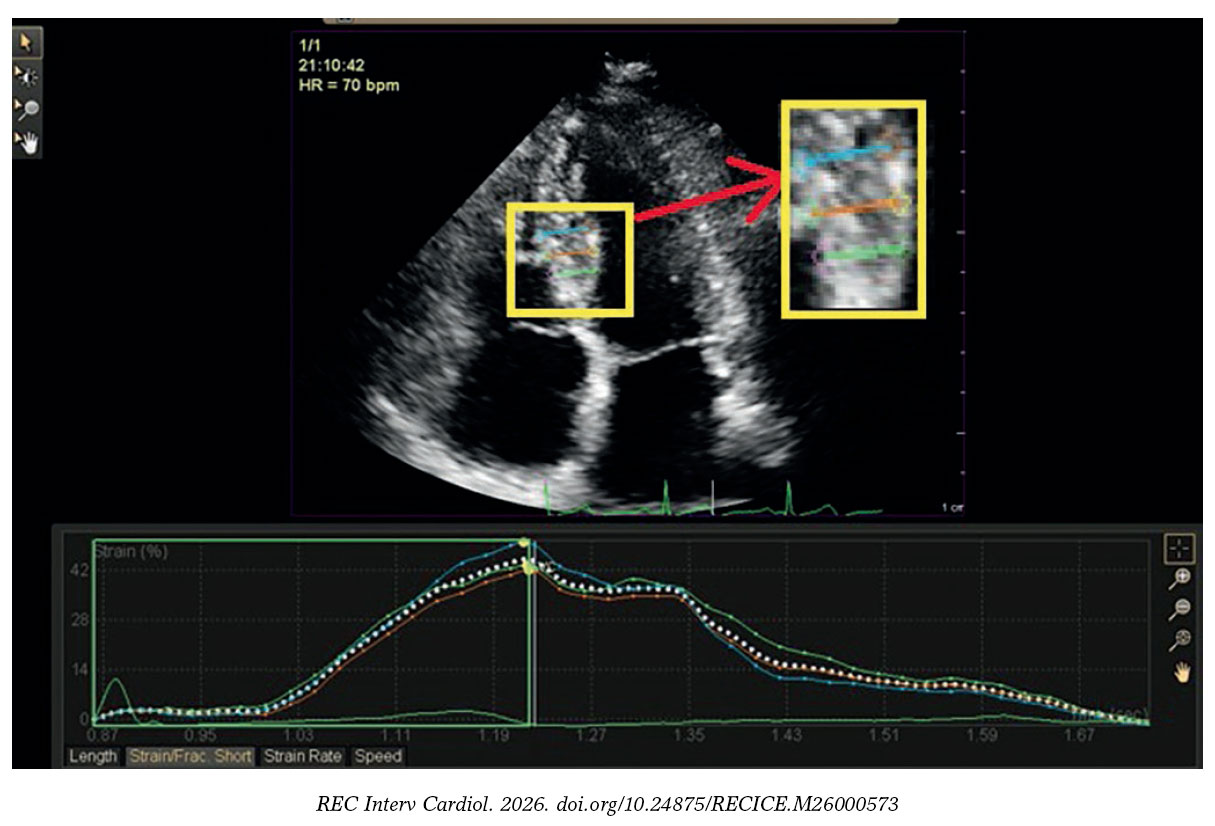

Figure 2. Regional radial strain analysis of a study participant with stable coronary artery disease showing 42% strain of the mid inferoseptal segment.